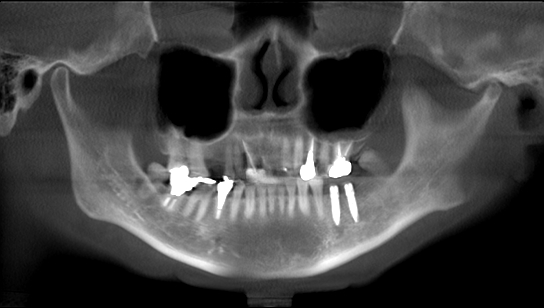

術前のパノラマになります

大きく奥歯がなくなっています